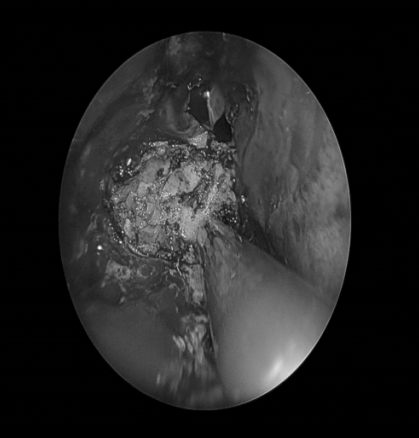

电子喉镜检查:鼻息肉(双)

4. 查体:双侧外耳道通常,双侧鼓膜完整,右侧鼓膜内陷明显,右侧鼓室内可见积液;外鼻无畸形,鼻中隔向左侧偏曲,双侧下鼻甲黏膜稍肿胀,双侧中鼻道见半透明荔枝肉样新生物,中鼻甲黏膜稍水肿;鼻咽部黏膜光滑,未见明显新生物